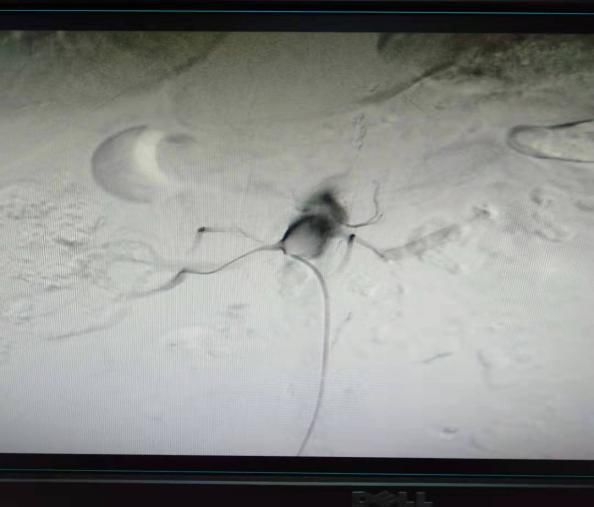

(6)2018年12月13日开展第一例颅内动脉瘤栓塞术。

患者:赵某  女性 48岁 河南省光山县

图片